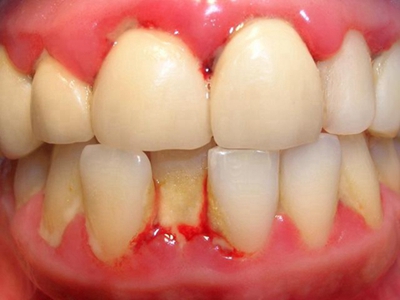

牙龈炎是发生于牙龈组织的炎症,患者可出现牙龈出血伴肿胀、发红、正常形态改变和偶尔不适等症状。本病主要由口腔卫生状况差导致,包括口腔不洁、牙菌斑等,诊断依据临床检查,治疗包括专业牙齿清洁和加强家庭口腔卫生。

牙龈炎可先引起牙齿与牙龈之间的沟(龈沟)加深,然后牙龈充血,炎症围绕一个或多个牙齿,伴牙龈乳头肿胀和易出血。一般无痛,可自行消退,也可维持轻度炎症数年。

牙龈炎常见的病因是口腔卫生差,不良的口腔卫生使牙菌斑沉积于牙齿与牙龈之间,造成龈沟加深,另外牙结石、不良修复体等也可造成牙龈炎的发生。